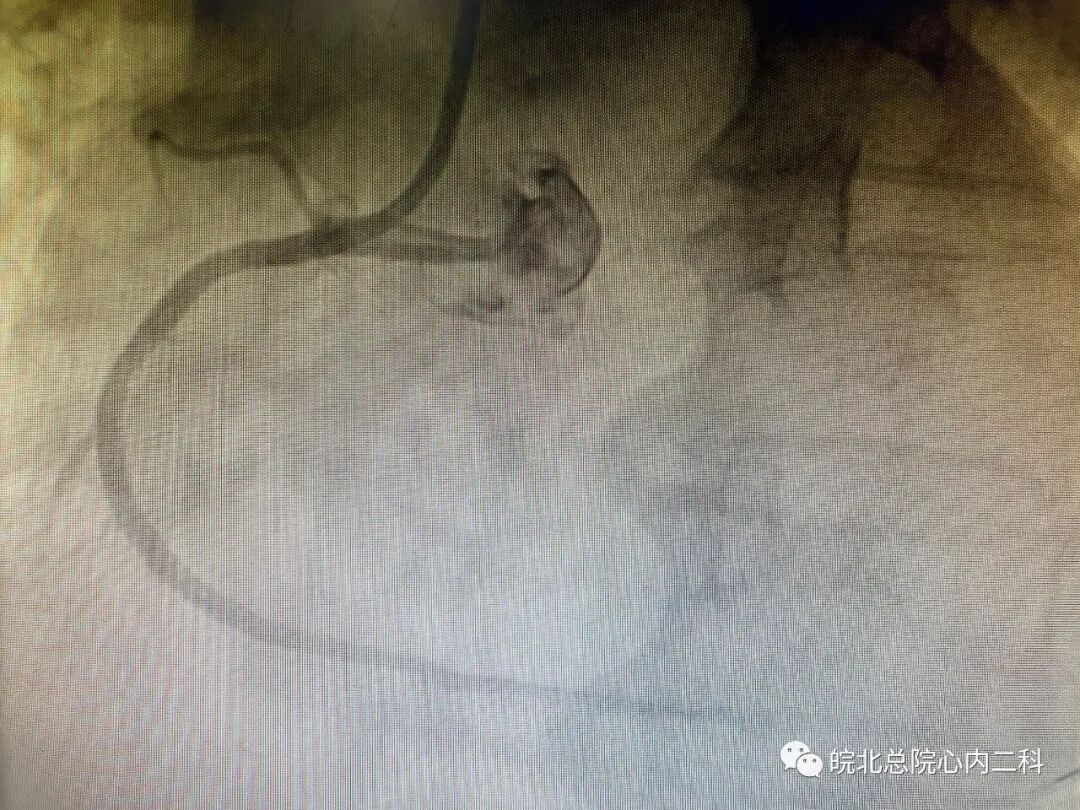

昨日皖北总院心内二科连续抢救两名急性下壁ST段抬高型心肌梗死患者,两名患者均以最短的时间接受了急诊介入治疗,其中一名患者35岁,打篮球后突发胸痛1小时入院,患者直接绕行病房,急诊冠脉造影右冠近中段完全闭塞。崔主任手术团队十分钟导丝通过开通血管,最快的挽救患者的存活心肌,改善患者的预后!目前两位患者生命体征尚平稳,近期可康复出院!